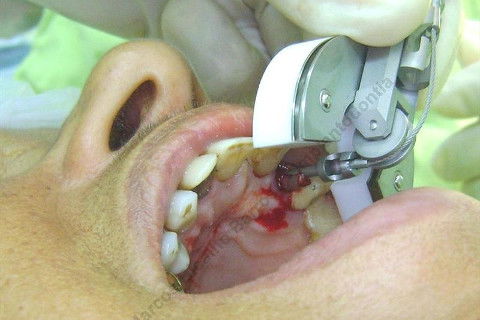

Paciente 66 anos, sexo feminino, procurou meus serviços para instalação de implante e coroa sobre implante na região do dente 22 com fratura radicular. Existem indicações para mais implantes mas a paciente está inrteressada no momento pela resolução deste caso.

Inicalmente estava planejado um implante cone morse 3.5 X 15,0 EX, mas resolvi experimentar um implante HI oferecido pelo vendedor da Bionnovation, como brinde (ele soube que estou preferindo o cone morse mas não trabalham com este sistema), e não consegui carga imediata neste implante. O travamento não foi satisfatório, ficou com um pouco mais de 20 N, menos de 25 N. Apesar desta ocorrência isto não significa que dará problema, apenas não fiz com carga imediata, aguardaremos 4 meses para a osseointegração.

Se o implante utilizado fosse o CM EX 3.5 X 15,0, além deste tipo de implante possuir característica autorosqueante, promovendo pelo seu design um melhor travamento, o seu comprimento de 15mm + 2mm infraósseo, conseguiríamos 6 mm de travamento em osso "virgem" (comprimento da raiz era de 11 mm) e travaria na cortical nasal. Mas este que usei, hexágono interno cônico, fica ao nível do rebordo; o maior que fabricam (comprimento de 15 mm), não apoiou em osso cortical e não é autorosqueante como o EX da Neodent.